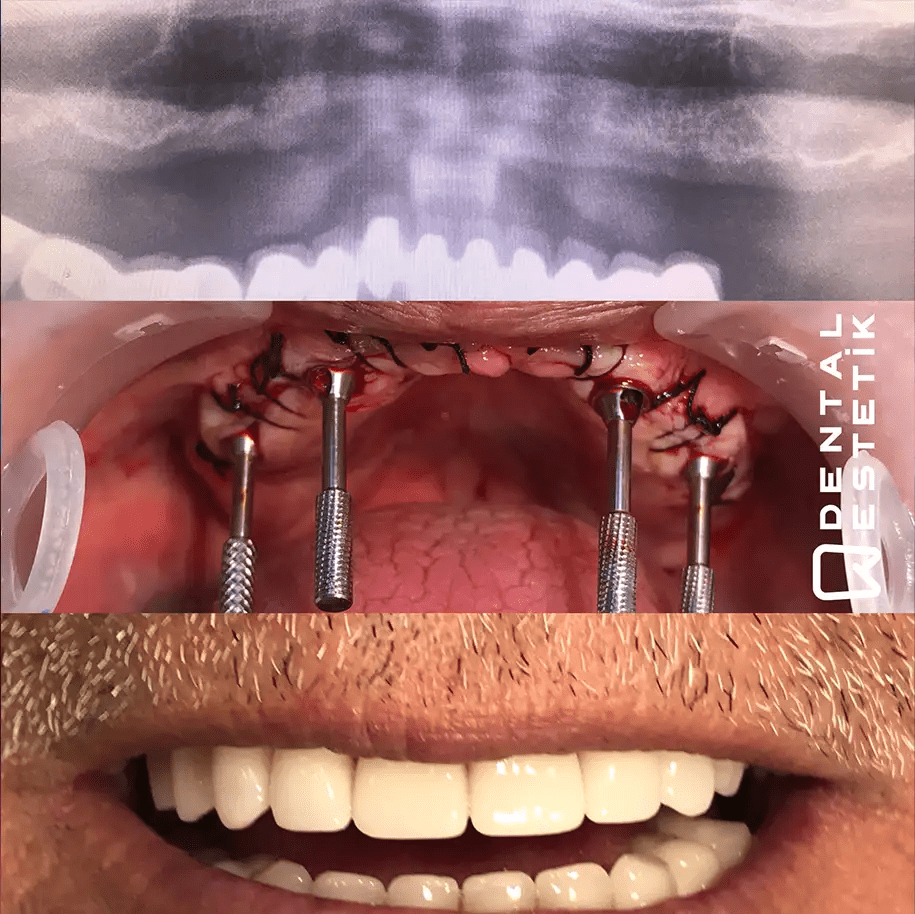

Dental Estetik Ağız ve Diş Sağlığı Polikliniği is a leading dental clinic located in Manisa, Turkey, committed to providing exceptional dental care with a focus on patient comfort and satisfaction. With over 15 years of experience and approximately 10,000 patients served, the clinic boasts a team of expert dentists, including Dt. Tuncer ÖZTÜRK, Dt. Recep SEVER, and Dt. Reyhan DİRMİLLİ, who utilize state-of-the-art technology such as CAD/CAM and 3D printing to deliver high-quality results. The clinic's comprehensive range of treatments includes dental implants, professional teeth whitening, root canal treatments, and specialized solutions like the All-on-Four and All-on-Six implant techniques, which offer innovative options for patients who have lost most or all of their teeth. In addition to its advanced dental services, Dental Estetik also provides a complete health tourism package, ensuring a hassle-free experience for international patients. This includes round-trip airfare, airport transfers, luxurious accommodations, and all essential dental treatments, allowing patients to focus solely on their health and well-being. The clinic emphasizes a patient-centered approach, crafting personalized treatment plans tailored to individual needs, and ensuring that every visit is a step towards achieving a confident and healthy smile.